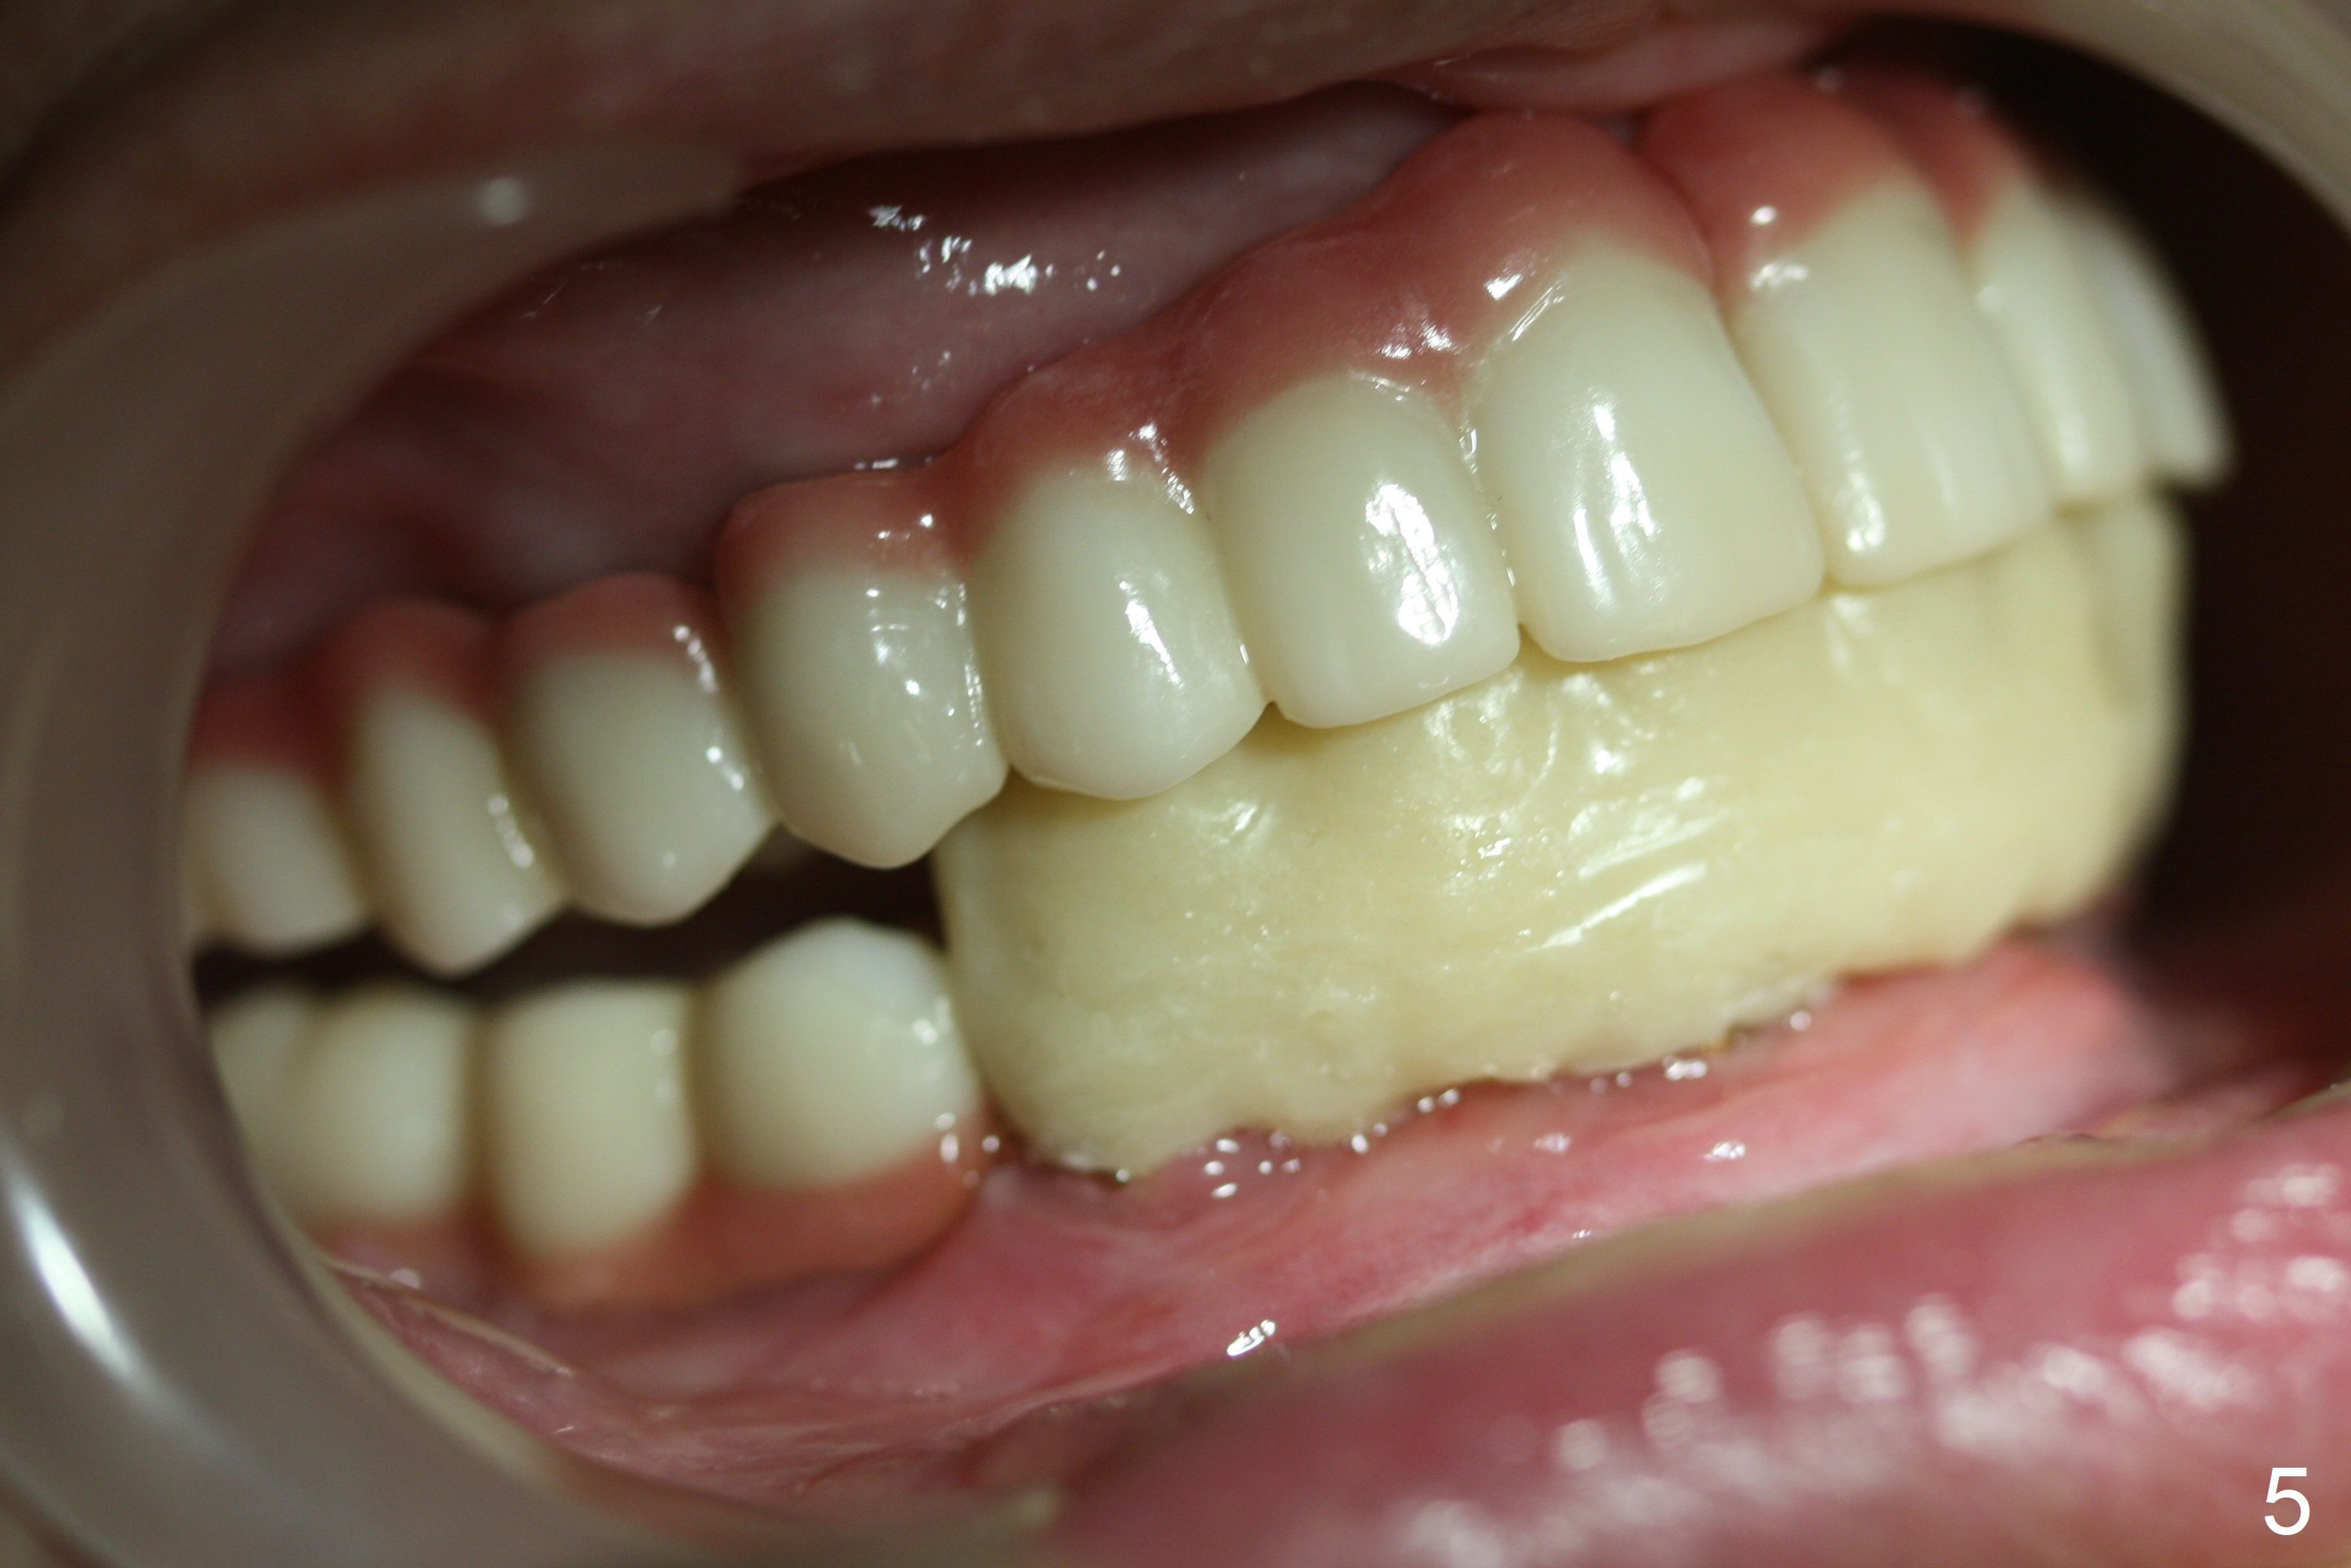

A 56-year-old woman with atrophic jaws requests redoing lower implant restoration (in function 1 year) for cosmetic reason and placing an implant at #19 (because she could not masticate on the left). Note the discrepancy between CR and CO (Fig.1,2). There is gingival hypertrophy at #31 (Fig.3), while the anterior restoration looks short with gingival recession (Fig.4). The patient is pleased instantly when lower anterior provisional is fabricated (Fig.5-7).